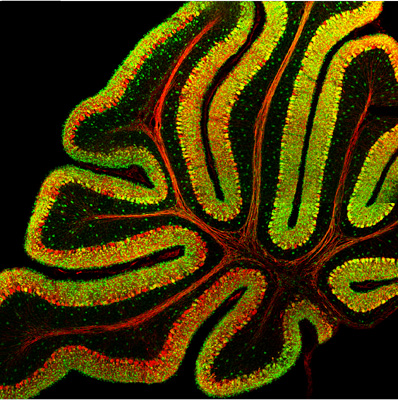

The hattip goes to Mind Hacks, who just featured the exhibit info in the post The Fire Within. Almost all The Beautiful Mind images use flourescence techniques, which we have shown before in Brainbows and More on Brainbow.

-Jean-Marc Fritschy, Purkinje cell in the cerebellum